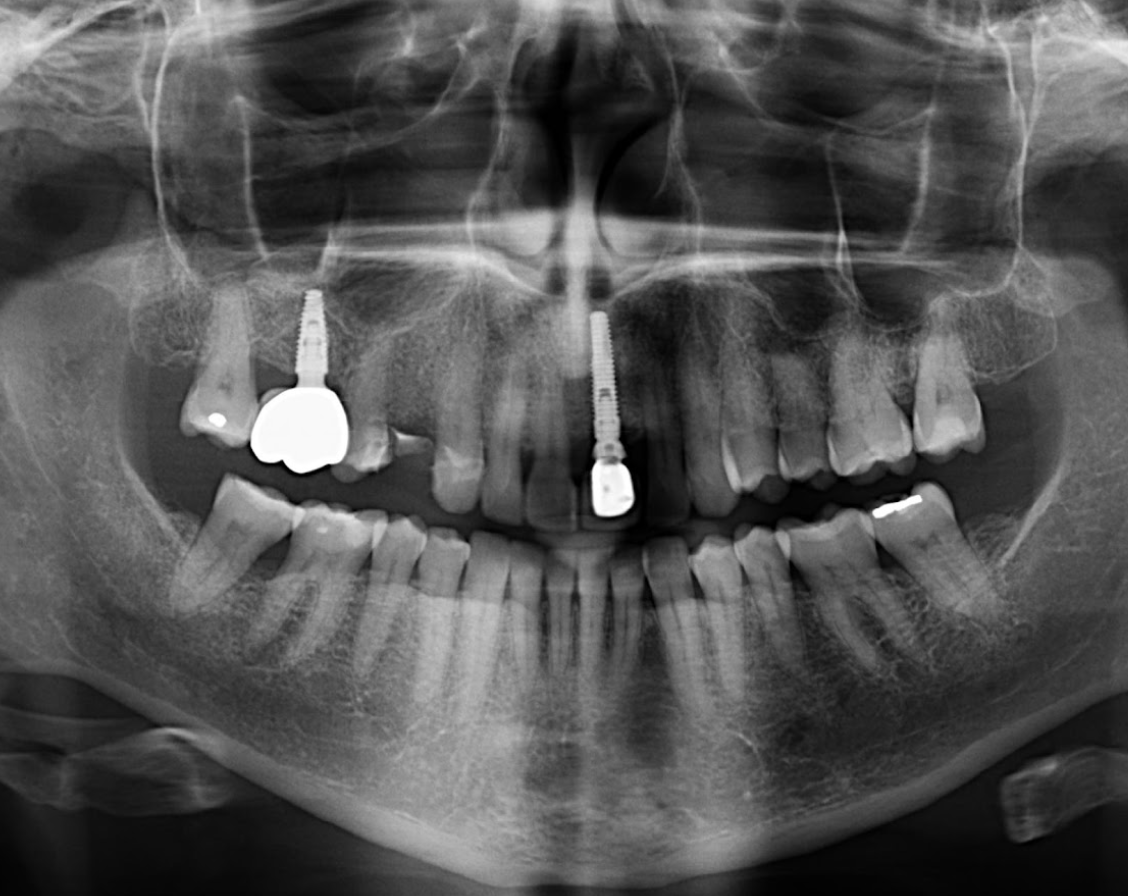

Paciente femenina de 51 años acude al Instituto para realizarse una tomografía volumétrica para rehabilitación oral, a la evaluación de la radiografía panorámica se observa neumatización de ambos seno maxilares, imagen radiopaca proyectada a nivel apical de la pieza 35 compatible con osteoesclerosis idiopática, múltiples restauraciones coronarias, presencia de dos implantes en zona de las piezas 16 y 21.

Radiografia Panorámica

A la evaluación de la tomografía de campo mediano (10 x 10) se observa una imagen hiperdensa que no se evidencia en la radiografía, de forma irregular y limites definidos localizada en tejido blando a nivel de piso de boca y de las piezas 36 y 35 compatible con sialolito submandibular.